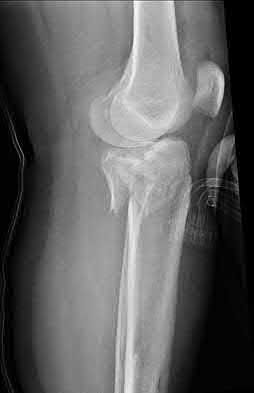

1. # A 32-year-old male sustains the injury shown in Figure A and undergoes treatment as shown in Figure B. Following placement of this implant, what is the best technique to confirm it is not too proud proximally?

1. Lateral radiograph of the knee

The safe zone for tibial nail placement as seen on radiographs is just medial to the lateral tibial spine on the anteroposterior radiograph and immediately adjacent and anterior to the articular surface as visualized on the lateral radiograph.

Tornetta et al specifically located the safe zone for nail entry in a study using fresh frozen cadaver knees. The authors found that the safe zone for nail placement is located 9.1+/-5 millimeters lateral to the midline of the plateau and three millimeters lateral to the center of the tibial tubercle. The width of the safe zone averaged 22.9 millimeters and was as narrow as 12.6 millimeters.

The starting point of the of the nail can be best viewed on the lateral knee radiograph, an example of which is shown in Illustration A. Illustration B shows the "sweet spot" for nail insertion as defined by Tornetta.